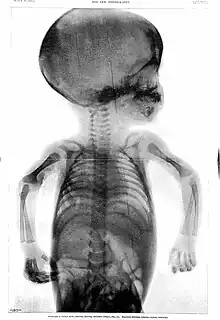

Rowland's career began in medical journalism while he was still a medical student when, in 1896, as Hart's intern, the year following the discovery of X-rays,[6] the BMJ appointed Rowland as "Special Commissioner" to produce a report on the clinical use of X-rays titled "Report on the Application of the New Photography in Medicine and Surgery."[3][6][lower-alpha 1] It was published in 17 parts between 8 February 1896 and 12 June 1897.[3] In May 1896, he founded the world's first X-ray journal, the Archives of Clinical Skiagraph, a radiology journal that preceded the British Journal of Radiology.[3][6] In the preface to the first issue, written in April 1896, he wrote that "the object of this publication is to put on record in permanent form some sort of the most striking applications of the new photography to the needs of medicine and surgery".[6] He coined the term "skiagraphy" to describe the making of X-ray pictures and wrote some of the early works on radiology.[3] Without any radiology experts or X-ray departments at the time, his journal became an essential reading.[6]